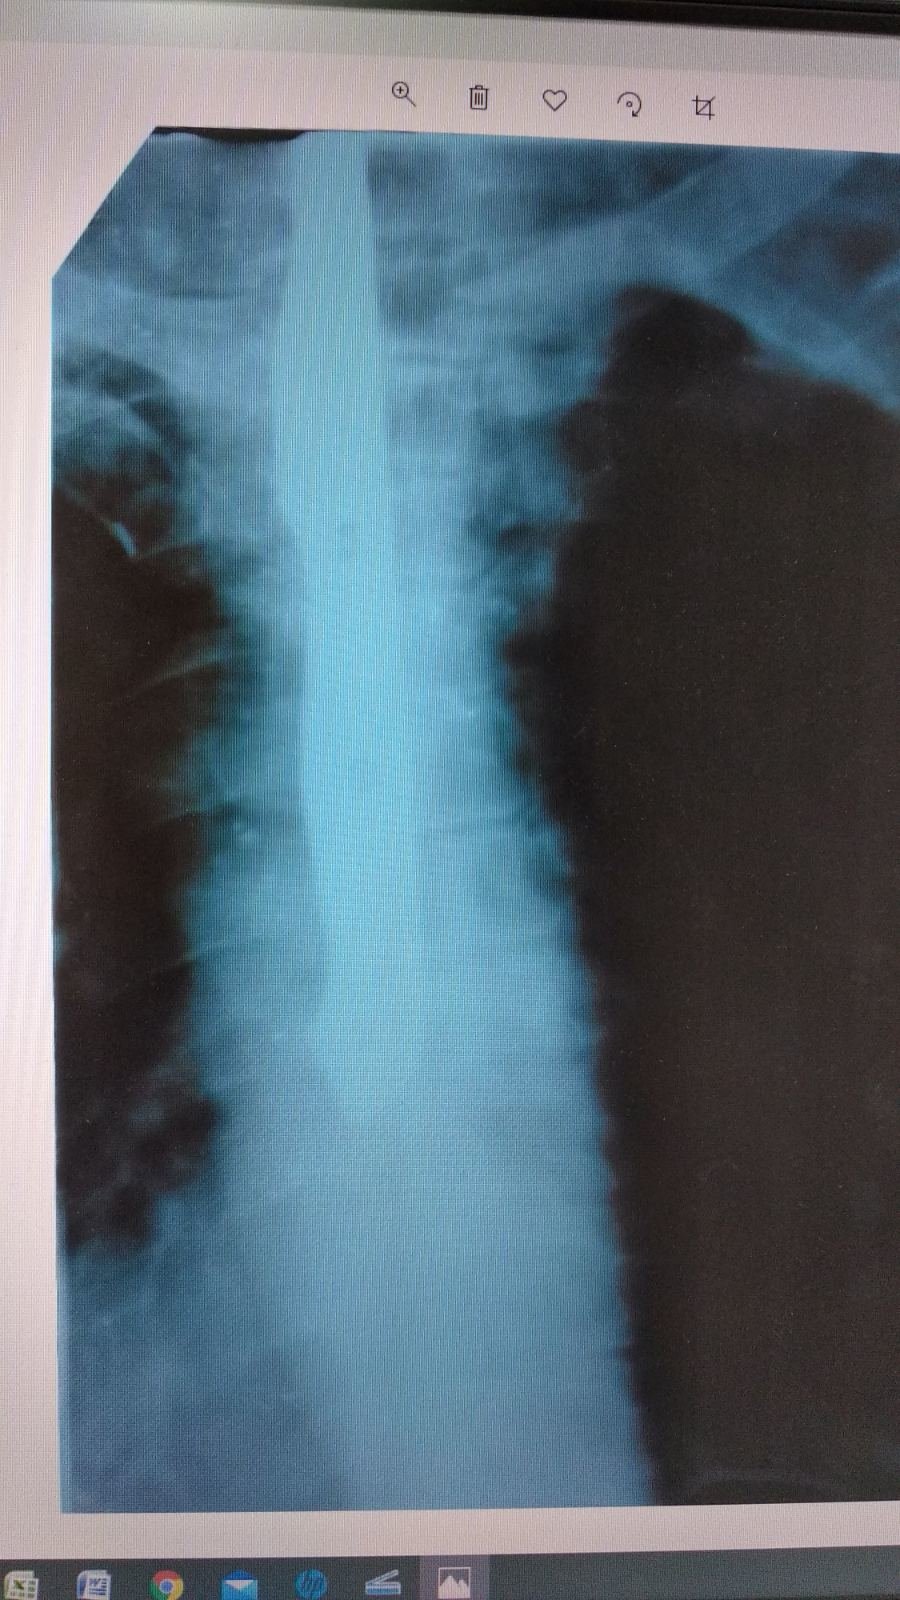

Он застрял после рвоты. ru.tsn.ua »

С помощью роботической системы сложное хирургическое вмешательство львовским врачам удалось совершить через четыре небольших прокола. focus.ua »

Мужчина обратился к медикам, но после проведенной операции он умер. 061.ua »